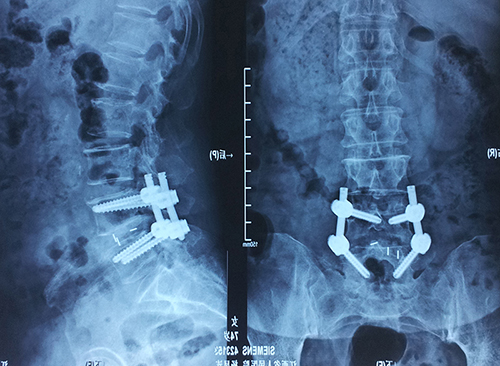

术后摄片

近日,我院骨一科陈钢主任、李宇旭医师完成了PIPELINE系统辅助下后外侧经椎间孔入路微创脊柱融合内固定手术(TLIF),成功为一例腰椎管狭窄患者实施手术,解除了困扰患者的严重腰腿痛和下肢瘫痪症状,填补了省内空白。

患者杨女士74岁,罹患腰腿痛已达3年余,伴有左足、左小腿麻木无力,行走困难。杨女士平时身体一直欠佳,多年的疾病折磨导致其身体状况较差,使手术风险加大,本人又惧怕传统开刀方式,故一直饱受疾病折磨。经多方咨询后慕名来到我院骨一科。陈钢主任、李宇旭医师经过仔细检查,认真研究,并与患者充分沟通,决定实施微创后外侧经椎间孔入路脊柱融合内固定手术。经充分的术前准备,手术顺利实施。术后不久,患者即感下肢疼痛缓解,肌力恢复,术后第3天即可下地行走。与传统手术相比,该手术切口小、创伤微小、出血少、疼痛轻、无需切割肌肉,术后恢复快,几乎不需卧床休息。

PIPELINE脊柱微创手术系统是目前国际上最新型的后入路手术微创系统之一,结合解剖学椎间融合器和VIPER2微创椎弓根置钉系统,能在微创条件下完成后路椎管减压、椎间植骨、固定钉的置入及锁定等腰椎后路内固定融合手术要求的所有复杂操作。该技术的完成不仅需要医院配置高清晰C-臂机,Medtrix椎间盘镜系统,PIPELINE脊柱微创手术系统(硬件配置总价值200万左右),更需要主刀医师坚实的开放性脊柱外科手术的基础,对局部解剖的充分认识,以及良好的微创操作的理念。2006年陈钢主任博士毕业后通过人才引进,从武汉同济医院调入江西省人民医院骨科工作,先后在省内率先开展了脊柱侧弯矫形术、上颈椎椎弓根螺钉固定术、后路一期颈胸段脊柱肿瘤切除重建内固定术等高难度开放性手术,同时开展了椎间盘镜下髓核摘除术、经皮椎体成形术,经皮椎弓根螺钉内固定技术治疗胸腰椎压缩性骨折手术等多项微创脊柱外科技术项目,突破了一个又一个技术瓶颈。PIPELINE-VIPER2脊柱微创手术的成功开展,标志着江西省微创脊柱外科技术再上新的台阶。